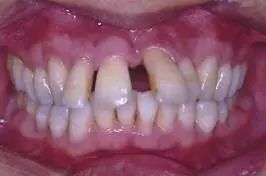

2、牙縫隙:可見前牙排列不緊密,稀疏,牙與牙之間存在間隙,嚴(yán)重影響患者的前牙美觀和容貌美觀。如圖2所示.

2,牙齒排列稀疏,存在間隙